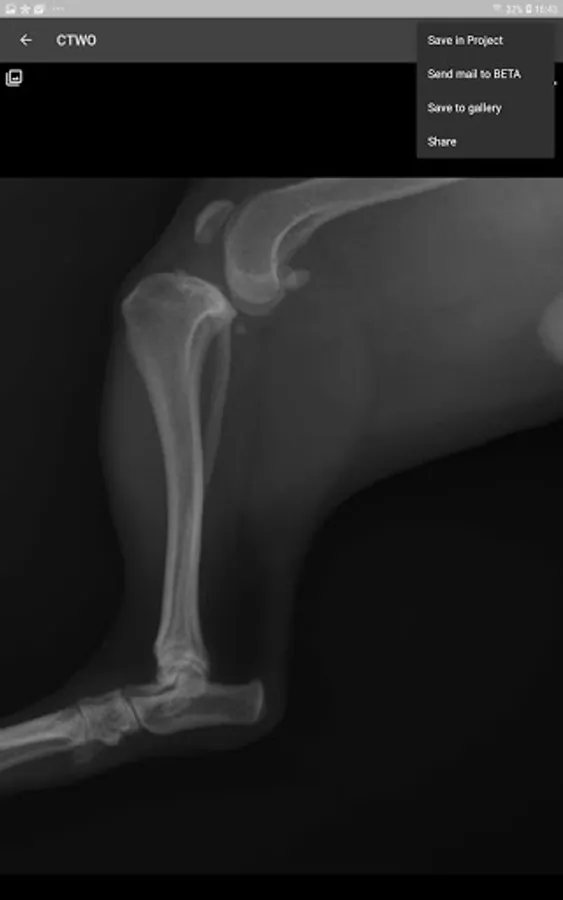

This is a useful tool for traumatology and orthopaedic surgical planning veterinary, including advanced techniques for treat canine anterior cruciate ligament (ACL) injuries (TPLO and CTWO).

· Comparison of preoperative plan and postoperative results.

5. Share your results

6. Save in project